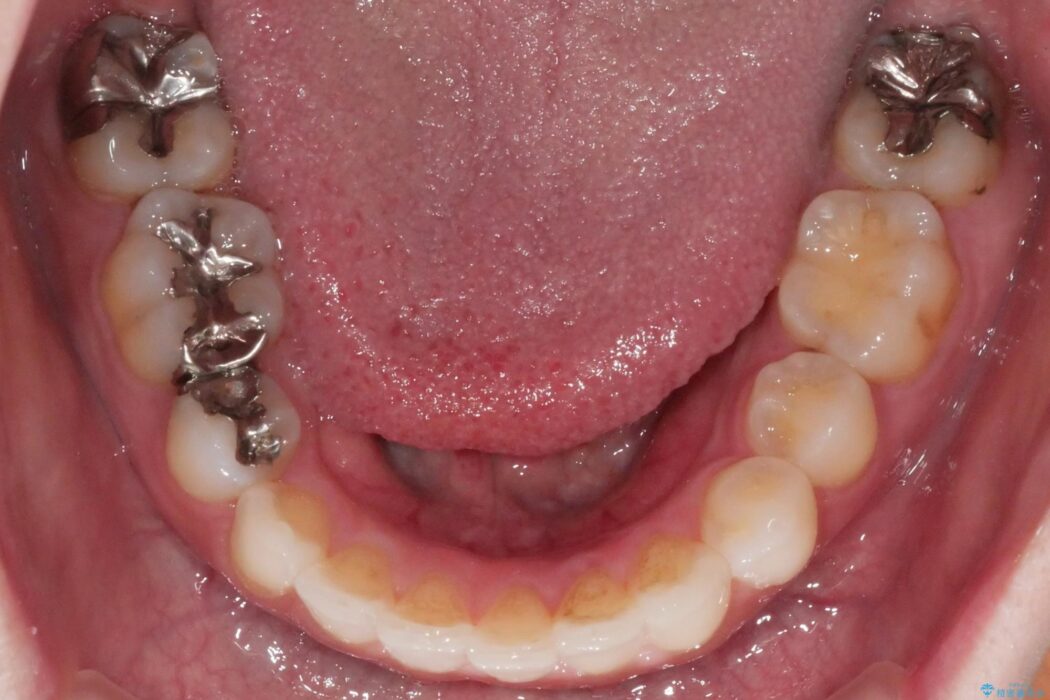

いつもでしたらマウスピース矯正をおすすめするのですが、自己管理の煩わしさから、目立たないワイヤー装置にて矯正治療を行うこととしました。

後戻りの程度としては軽度なので、治療期間としては短く終えることが出来ました。

前歯の正中線も改善され大変満足していただきました。